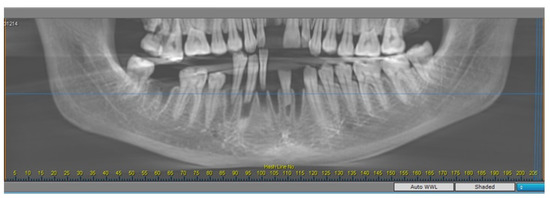

2.2. Radiomorphometric Assessments